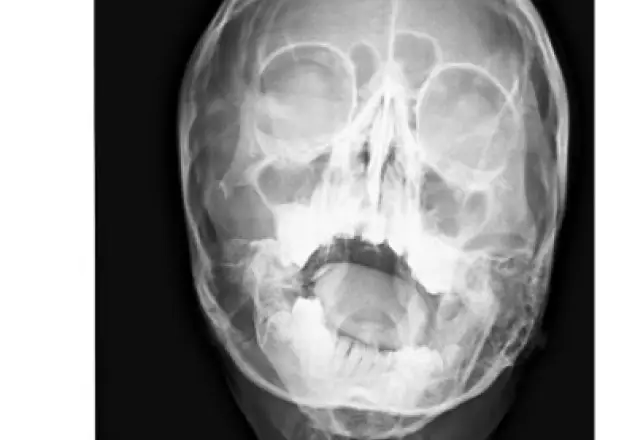

PA skull radiograph revealed an asymmetry on the right side with hypoplastic ramus, hypoplastic condylar head and aplastic coronoid process. The similar findings were confirmed by CT scan. Final diagnosis: Hemifacial Microsomia on right side OMENS Classification: O0M2BE3N71S2Management Immediate treatment: Orthodontic Opinion Planned treatment: Mandibular distraction osteogenesis.